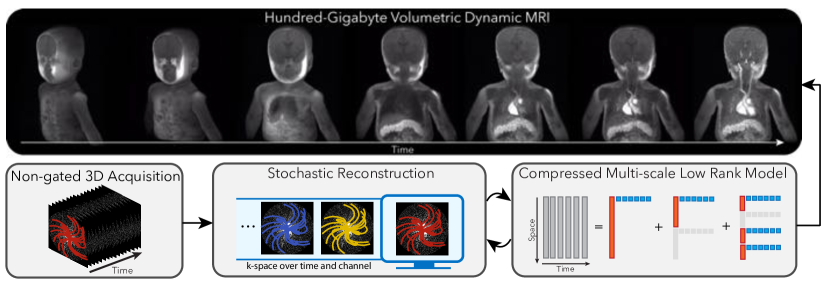

Theory and Methods: The problem considered here requires recovering hundred-gigabytes of dynamic volumetric image data from a few gigabytes of k-space data, acquired continuously over several minutes. This reconstruction is vastly under-determined, heavily stressing computing resources as well as memory management and storage. To overcome these challenges, we leverage intrinsic three dimensional (3D) trajectories, such as 3D radial and 3D cones, with ordering that incoherently cover time and k-space over the entire acquisition. We then propose two innovations: (1) A compressed representation using multi-scale low rank matrix factorization that constrains the reconstruction problem, and reduces its memory footprint. (2) Stochastic optimization to reduce computation, improve memory locality, and minimize communications between threads and processors. We demonstrate the feasibility of the proposed method on DCE imaging acquired with a golden-angle ordered 3D cones trajectory and pulmonary imaging acquired with a bit-reversed ordered 3D radial trajectory. We compare it with “soft-gated” dynamic reconstruction for DCE and respiratory resolved reconstruction for pulmonary imaging.

We propose two innovations to overcome these reconstruction challenges: (1) a compressed representation using the multi-scale low rank matrix factorization (MSLR) [31] that both constrains the reconstruction problem and reduces its memory footprint, and (2) stochastic optimization to reduce computation, improve memory locality and minimize communications between threads and processors.

To further reduce computation, we propose using stochastic gradient descent (SGD) [36] for reconstruction. SGD is commonly used nowadays in machine learning to efficiently optimize over large-scale datasets for training neural networks. Inspired by this use, we apply SGD to large-scale volumetric dynamic MRI reconstruction. SGD allows us to reduce the number of non-uniform fast Fourier transforms (NUFFT) from thousands-per-iteration to a single one per iteration. In particular, incorporating stochastic optimization for the proposed method cuts down the reconstruction time from weeks to hours, and will be described in more detail in Section 2.4.

Here we adopt the MSLR representation that generalizes the above mentioned LR models to represent dynamics at multiple scales. In MSLR, the spatiotemporal matrix is modelled as a sum of block-wise low rank matrices with increasing scales of block sizes, as illustrated in Figure 1. This allows us to combine the benefits of both LR and LLR, using the decomposition technique introduced in L+S.